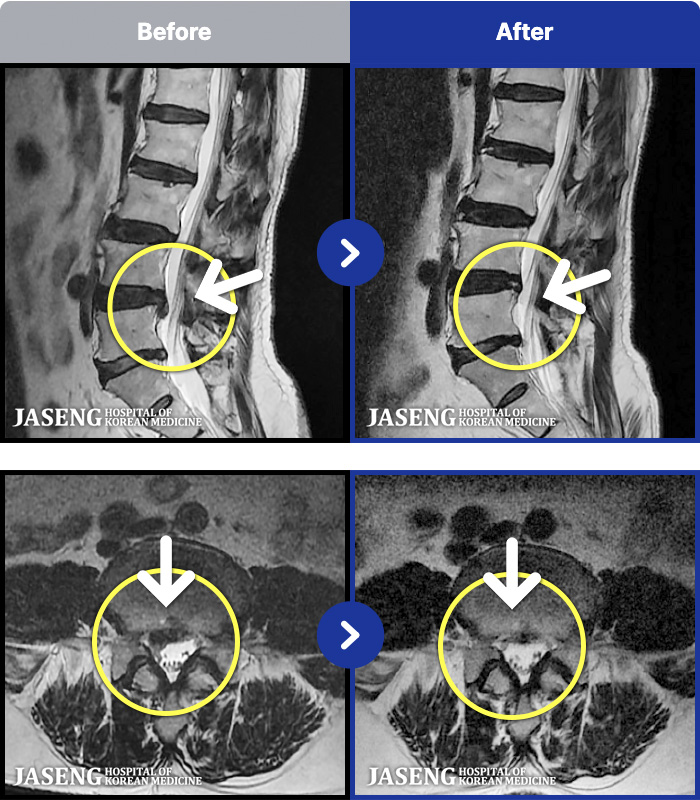

MRI ġ

1,240 MRI ũ ʸ Ȯϼ.

㸮 ϻ .